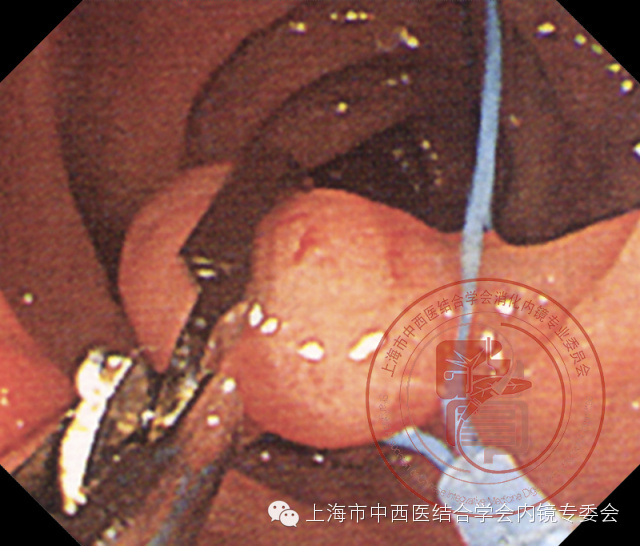

双钳道带蒂息肉尼龙套扎操作

2、操作者在其中一个工作通道内插入尼龙圈套释放器,当塑料外套管出现在视野中肠镜先端部后,嘱助手将尼龙圈套器从塑料外套管内缓慢伸出,对准病变套入。

伸出鼠齿钳

3、操作者在另一个工作通道内插入鼠齿钳,在尼龙圈套上方咬夹息肉端部向上向左侧缓慢提拉,暴露出息肉蒂部。

提拉息肉

4、随后操作者将尼龙圈套尽量靠近息肉蒂部,并靠向肠壁。嘱助手一边缓慢朝助手方向拉移塑料外套管,一边缓慢收紧释放装置,这时可以看到塑料外套管内的塑料固定器向前推移,收紧息肉蒂部。

收紧尼龙圈套